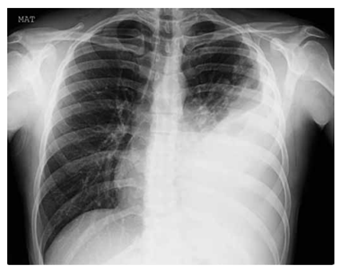

Leia o caso clínico a seguir para responder à questão:

Paciente do sexo masculino, 58 anos, tabagista de 40

maços/ano, portador de DPOC moderado.

Procura pronto-socorro com febre há 3 dias, tosse produtiva com expectoração purulenta e dispneia progressiva.

Nas últimas 6 horas, evoluiu com rebaixamento do sensório e intensa dificuldade respiratória. O exame físico

na sala de emergência apresenta: PA: 92 × 60 mmHg;

FC: 128 bpm; FR: 38 irpm; SatO₂: 82% em cateter nasal

5 L/min; T: 38,6 °C.

Escala de Glasgow: 12.

Estertores crepitantes difusos em hemitórax esquerdo e

abolido em base.

Uso de musculatura acessória e tiragem intercostal.

Apresenta exames complementares: leucócitos: 18.400/mm³;

creatinina: 1,9 mg/dL.

Gasometria em O₂: 5 L/min; pH: 7,28; PaO₂: 52 mmHg;

PaCO₂: 58 mmHg; HCO₃⁻: 20 mEq/L; relação PaO₂/

FiO₂:110.

Radiografia de tórax a seguir: